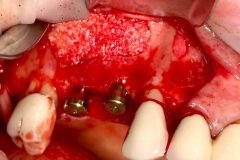

Implants placed using a digitally planned stackable surgical guide following alveolectomy, ensuring ideal positioning and a stable foundation for full-arch restoration.